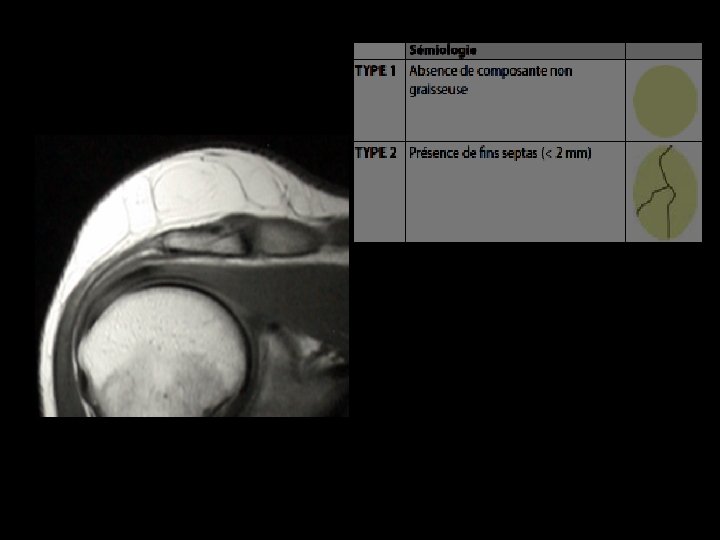

IRM : Cas particuliers • Capsule fibreuse en hyposignal sur l'ensemble des séquences • Fins septa réguliers conjonctivo-vasculaires, toujours d'épaisseur inférieure à 2 mm coupe axiale pondérée en. T 2 : visualisation de fins septa (flèches) au sein de la masse graisseuse homogène et en hypersignal

TUMEURS GRAISSEUSES BENIGNES LIPOME Localisation superficielle Taille < 5 cm Homogène Sépta < 2 mm Pas de nodules MALIGNES LIPOSARCOME BIEN DIFFERENCIE Localisation sous aponévrotique Taille >5 cm Hétérogène Sépta épais Éléments nodulaires et tissulaires